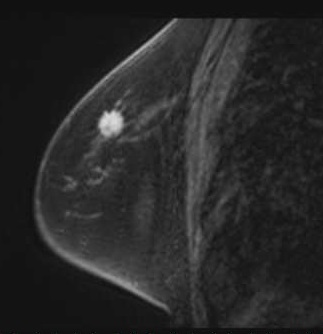

MRI検査

MR検査はがん診療において、CT検査と比較してより詳細な検査が可能です。

各臓器において浸潤範囲を描出することができ、治療範囲の決定のための広がり診断をすることができます。MRI検査は検査時間が長く、撮像できる範囲に制限があります。

MRI検査では造影剤が使用されます。

乳房造影MRI検査画像